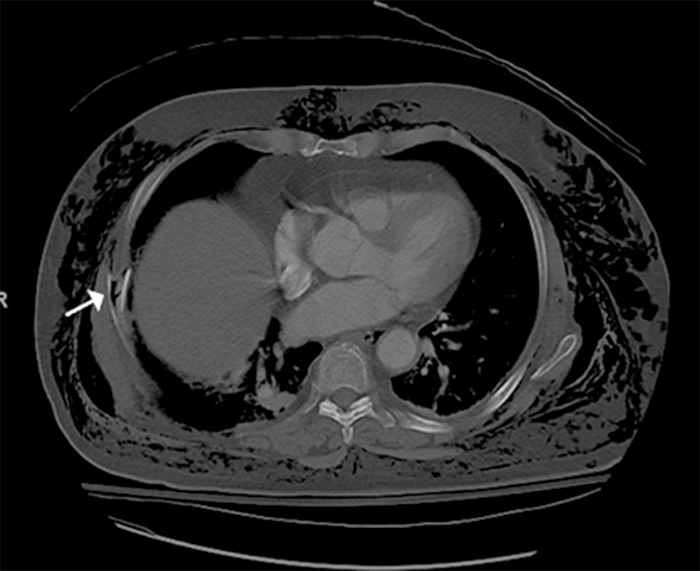

On arrival at our hospital, the patient had severe subcutaneous emphysema. She was hemodynamically normal, saturating 95% on a 3 L nasal cannula. Her imaging revealed comminuted and displaced fractures of right-sided ribs 7 through 9 (Figures 1, 2, and 3).

Figure 1. Comminuted Right Lateral Seventh Rib Fracture (white arrow). Published with Permission